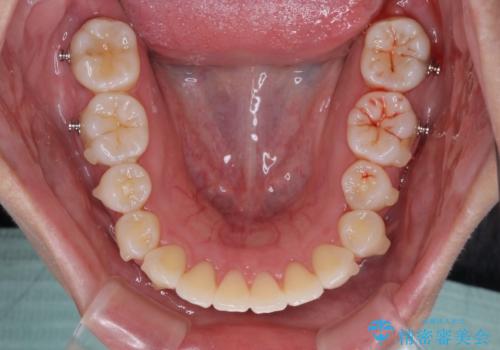

上下顎ともに歯列全体の後方移動とIPR(歯と歯の間を削る)によってデコボコが解消するように設計し、インビザラインにより治療を行うこととしました。

上下ともにIPRを積極的に行っているため、舌の突出癖をしっかりと改善できないと、後戻りにより隙間やデコボコが早い段階で発現することになるため、舌のトレーニングが非常に大切になります。